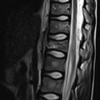

List and describe all Modic types

Type 1 - Edema (t1 down, t2 is up)

Fibrovascular changes

Type 2- Fatty change (T1 and T2 both UP/bright)

Fatty yellow marrow

Type 3 - sclerosis (T1 and T2 are down

Sclerosing of bone